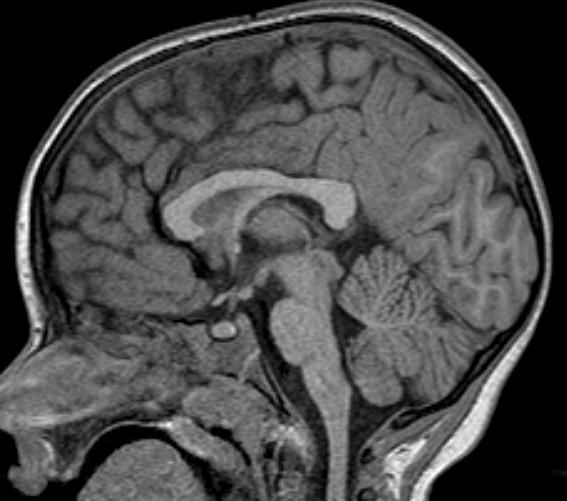

Note the CSF flow dephasing through the defect in the floor of the third ventricle.